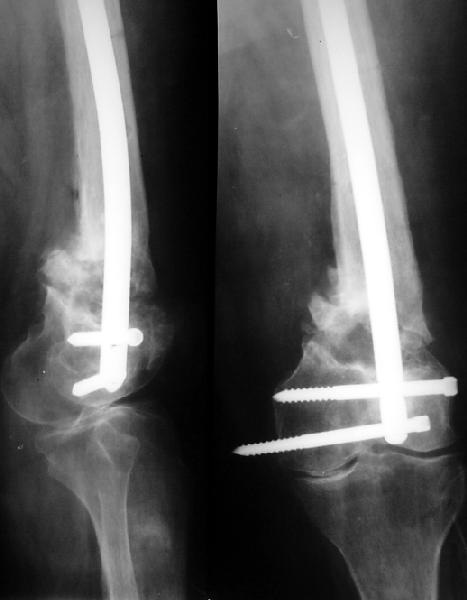

Здесь вполне можно не вмешиваться открыто. Сделать fixator-assisted

nailing. Все закрыто убрать. Хорошо восстановить ось. Через медуллярный

канал ручными развертками освежить концы отломков. И заштифтовать. Раз

уже был ретроградный стержень - то ретроградно. Я бы взял большеберцовый

гвоздь, чтобы ввести винты в разных плоскостях. Ну и гвоздь потолще, и

винты 6 мм.

Вот давний пример похожего ложного сустава после неоднократных

остеосинтезов.